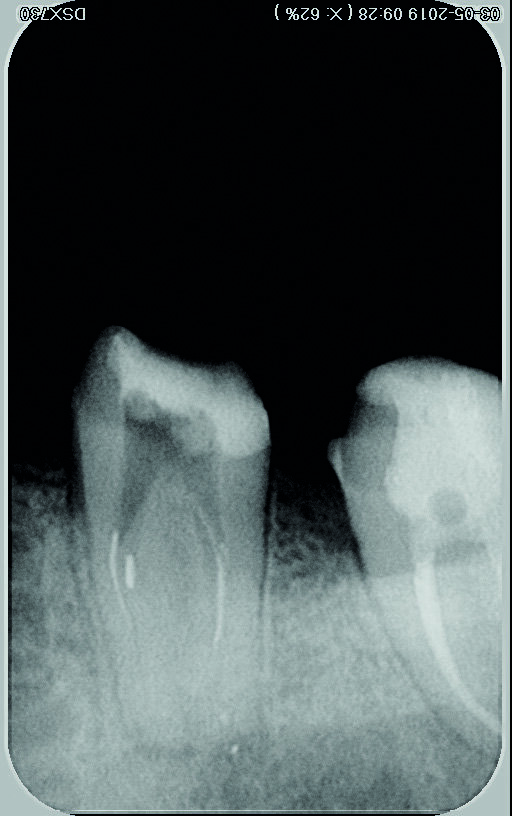

Le système de lasso choisi est le dispositif EndoCowboy en raison des caractéristiques et de la résistance du fil (fil de 0,1 mm en acier inoxydable étiré ayant une excellente résistance à la rupture, et tube de 0,4 mm ; Köhrer Medical Engineering). Conformément aux instructions du fabricant (Figs. 8 et 9), le dispositif est manipulé par deux praticiens travaillant en commun — l’un étant chargé d’observer au microscope la position de la boucle du lasso autour du fragment fracturé, et l’autre de manipuler le dispositif (serrage du lasso autour du fragment. Après avoir solidarisé le fragment et la boucle, l’ensemble est alors retiré par de légers mouvements de va-et-vient verticaux (Figs. 10–13). Tous les canaux sont instrumentés avec des limes D-Finder de taille 8, 10, 12 et 15 (MANI) pour obtenir manuellement une trajectoire de glissement (glide path). Le nettoyage et la mise en forme de tous les canaux radiculaires sont réalisés à l’aide de limes Silk (MANI) de taille croissante (jusqu’à 25/0.06) et du moteur endodontique Tri Auto ZX2 (Morita). Un protocole d’irrigation à l’hypochlorite de sodium à 5,25 % est assuré tout au long du traitement. L’irrigation finale est accomplie avec une solution d’EDTA à 17 % et d’hypochlorite de sodium à 5,25 %, activée par une technique manuelle d’activation dynamique. La technique de condensation hydraulique est utilisée pour réaliser l’obturation avec des cônes de gutta-percha à 4 % et le ciment de scellement BioRoot RCS (Septodont) (Figs. 14–16). La cavité pulpaire est scellée au moyen d’un ciment verre ionomère modifié par adjonction de résine, Ionoseal (VOCO), et une restauration provisoire est préparée.

Fig. 13 : Radiographie après retrait du fragment.

Fig. 14 : Obturation avec un ciment de scellement biocéramique.

Figs. 15 et 16 : Radiographie après obturation.